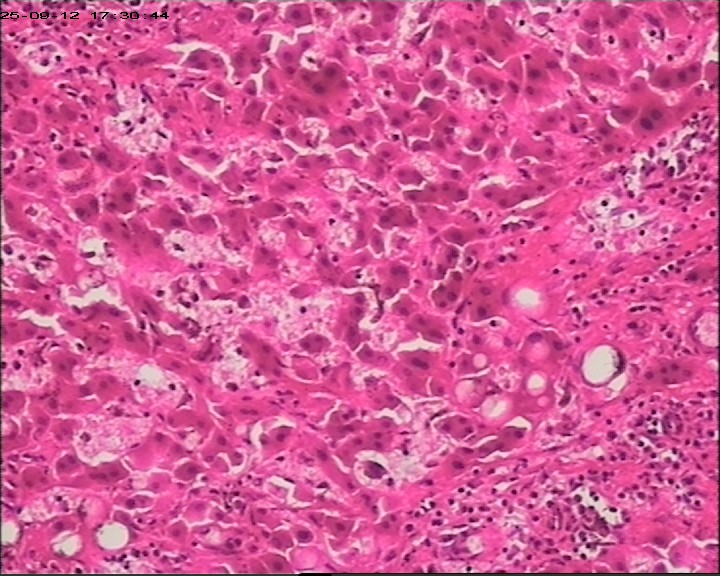

性别年龄47岁临床诊断肝占位性质待查,肝棘球蚴病?

大体所见肝组织一块,大小为20*18*15cm,切面多房囊性,部分内含坏死样物。

建议:描述性病理诊断!(感觉符合棘球蚴病病理改变,但未见明显的直接证据!)

大体检查有没有看到粉皮样的角质膜?取角质膜在镜下找到头节有助于诊断。